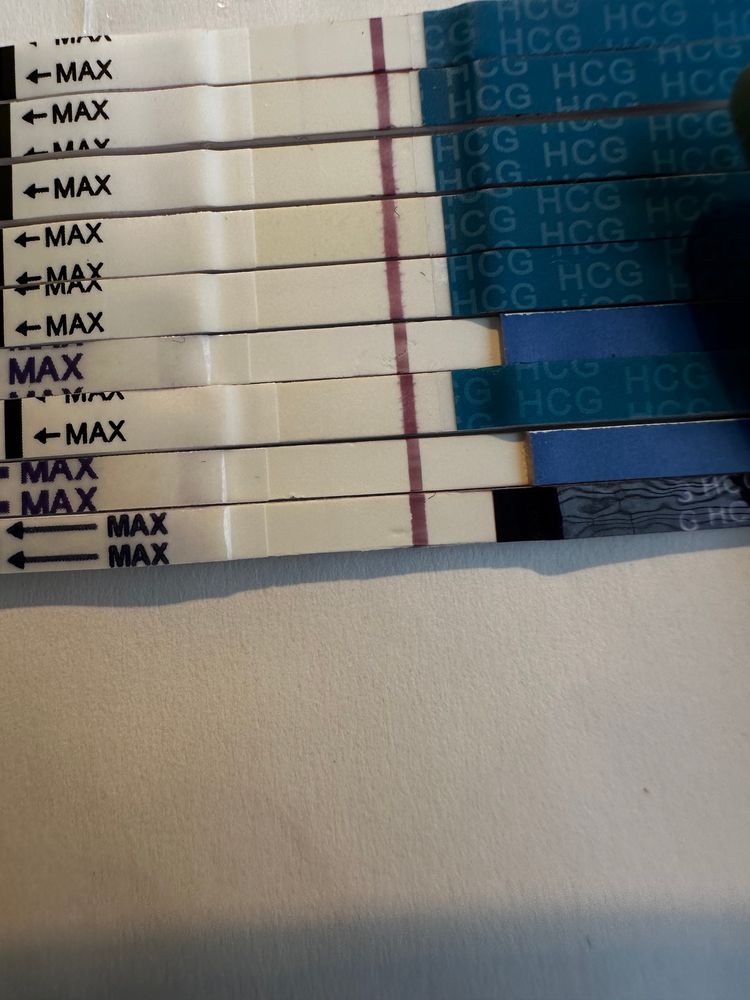

Что вы видите и видите ли вообще 😁

я вижу здесь розовенькие полосочки но честно им не верю что вы скажете? Последний тест прогнала через прогу полоска вроде мне не мерещиться не знаю даже

Таня Орозова, верхние там есть полоски это хгч укол снизу вверх мне вот интересно на нижнем видно или нет его еще так сложно сфоткать 🥲🤦🏻♀️

Li , на нижних 3-х есть тень какая-то. А сколько дней после укола прошло и в какой дозировке был?

Укол уже вышел так как один тестам вроде как вообще чистый мне вот интересно реагент это или что склоняюсь больше к реагенту